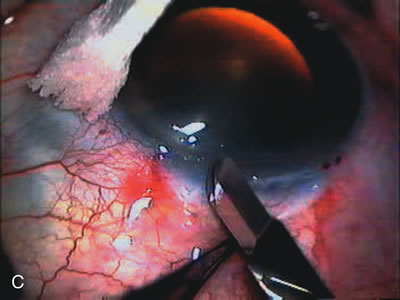

Fig. 3. Partial bleb failure following clear corneal phacoemulsification with foldable IOL. A. Preoperative bleb appearance prior to temporal lens extraction. Preoperative IOP was 12 mm Hg on no antiglaucoma medications. Time from 5-FU trabeculectomy surgery to lens extraction was one year. B. Bleb appearance 2 months after clear corneal cataract surgery with topical anesthesia. Following lens extraction, increased vascularity was noted along with decreased size of the filtering bleb. IOP increased to 20 mm Hg as early as 2 weeks after surgery, necessitating topical antiglaucoma therapy. C. High magnification view of bleb before lens extraction demonstrates diffuse pale bleb. D. High magnification view of bleb 2 months after surgery. There are vessels surrounding the nasal side of the bleb and the overall bleb size is smaller.

Fig. 1. The anatomic advantage of small incision cataract surgery for the glaucoma patient. A. Long-term bleb function with a large cataract incision is difficult to achieve with either ECCE-trabeculectomy or trabeculectomy followed later by ECCE. This bleb failed to form sufficiently when combined with large incision ECCE. The inflammation, bleeding, and long-term wound healing with stimulation of fibroblasts associated with this technique are more likely to cause bleb failure. In addition, the increased iris manipulation necessary to deliver the nucleus and subsequent iris repair adds to the long-term breakdown of the blood aqueous barrier. B and C. Two-site phacotrabeculectomy has the advantage of small incision cataract surgery combined with separate site trabeculectomy. The incision size is one third the size of the standard ECCE. The inflammation is less severe, and cataract wound healing is confined to the temporal area. Visual rehabilitation with phacoemulsification and foldable IOL is much faster. Phacoemulsification allows successful lens extraction even in the unfriendly environment of a smaller pupil compared with ECCE. The trabeculectomy is performed in an entirely different site, well away from the wound healing associated with temporal phacoemulsification. The likelihood of this filter functioning long-term is greater than with ECCE-trabeculectomy. D. The surgeon also has the option of single-site phacotrabeculectomy with foldable IOL. Both the lens extraction and trabeculectomy are performed through one small 3.5-mm limbal incision.